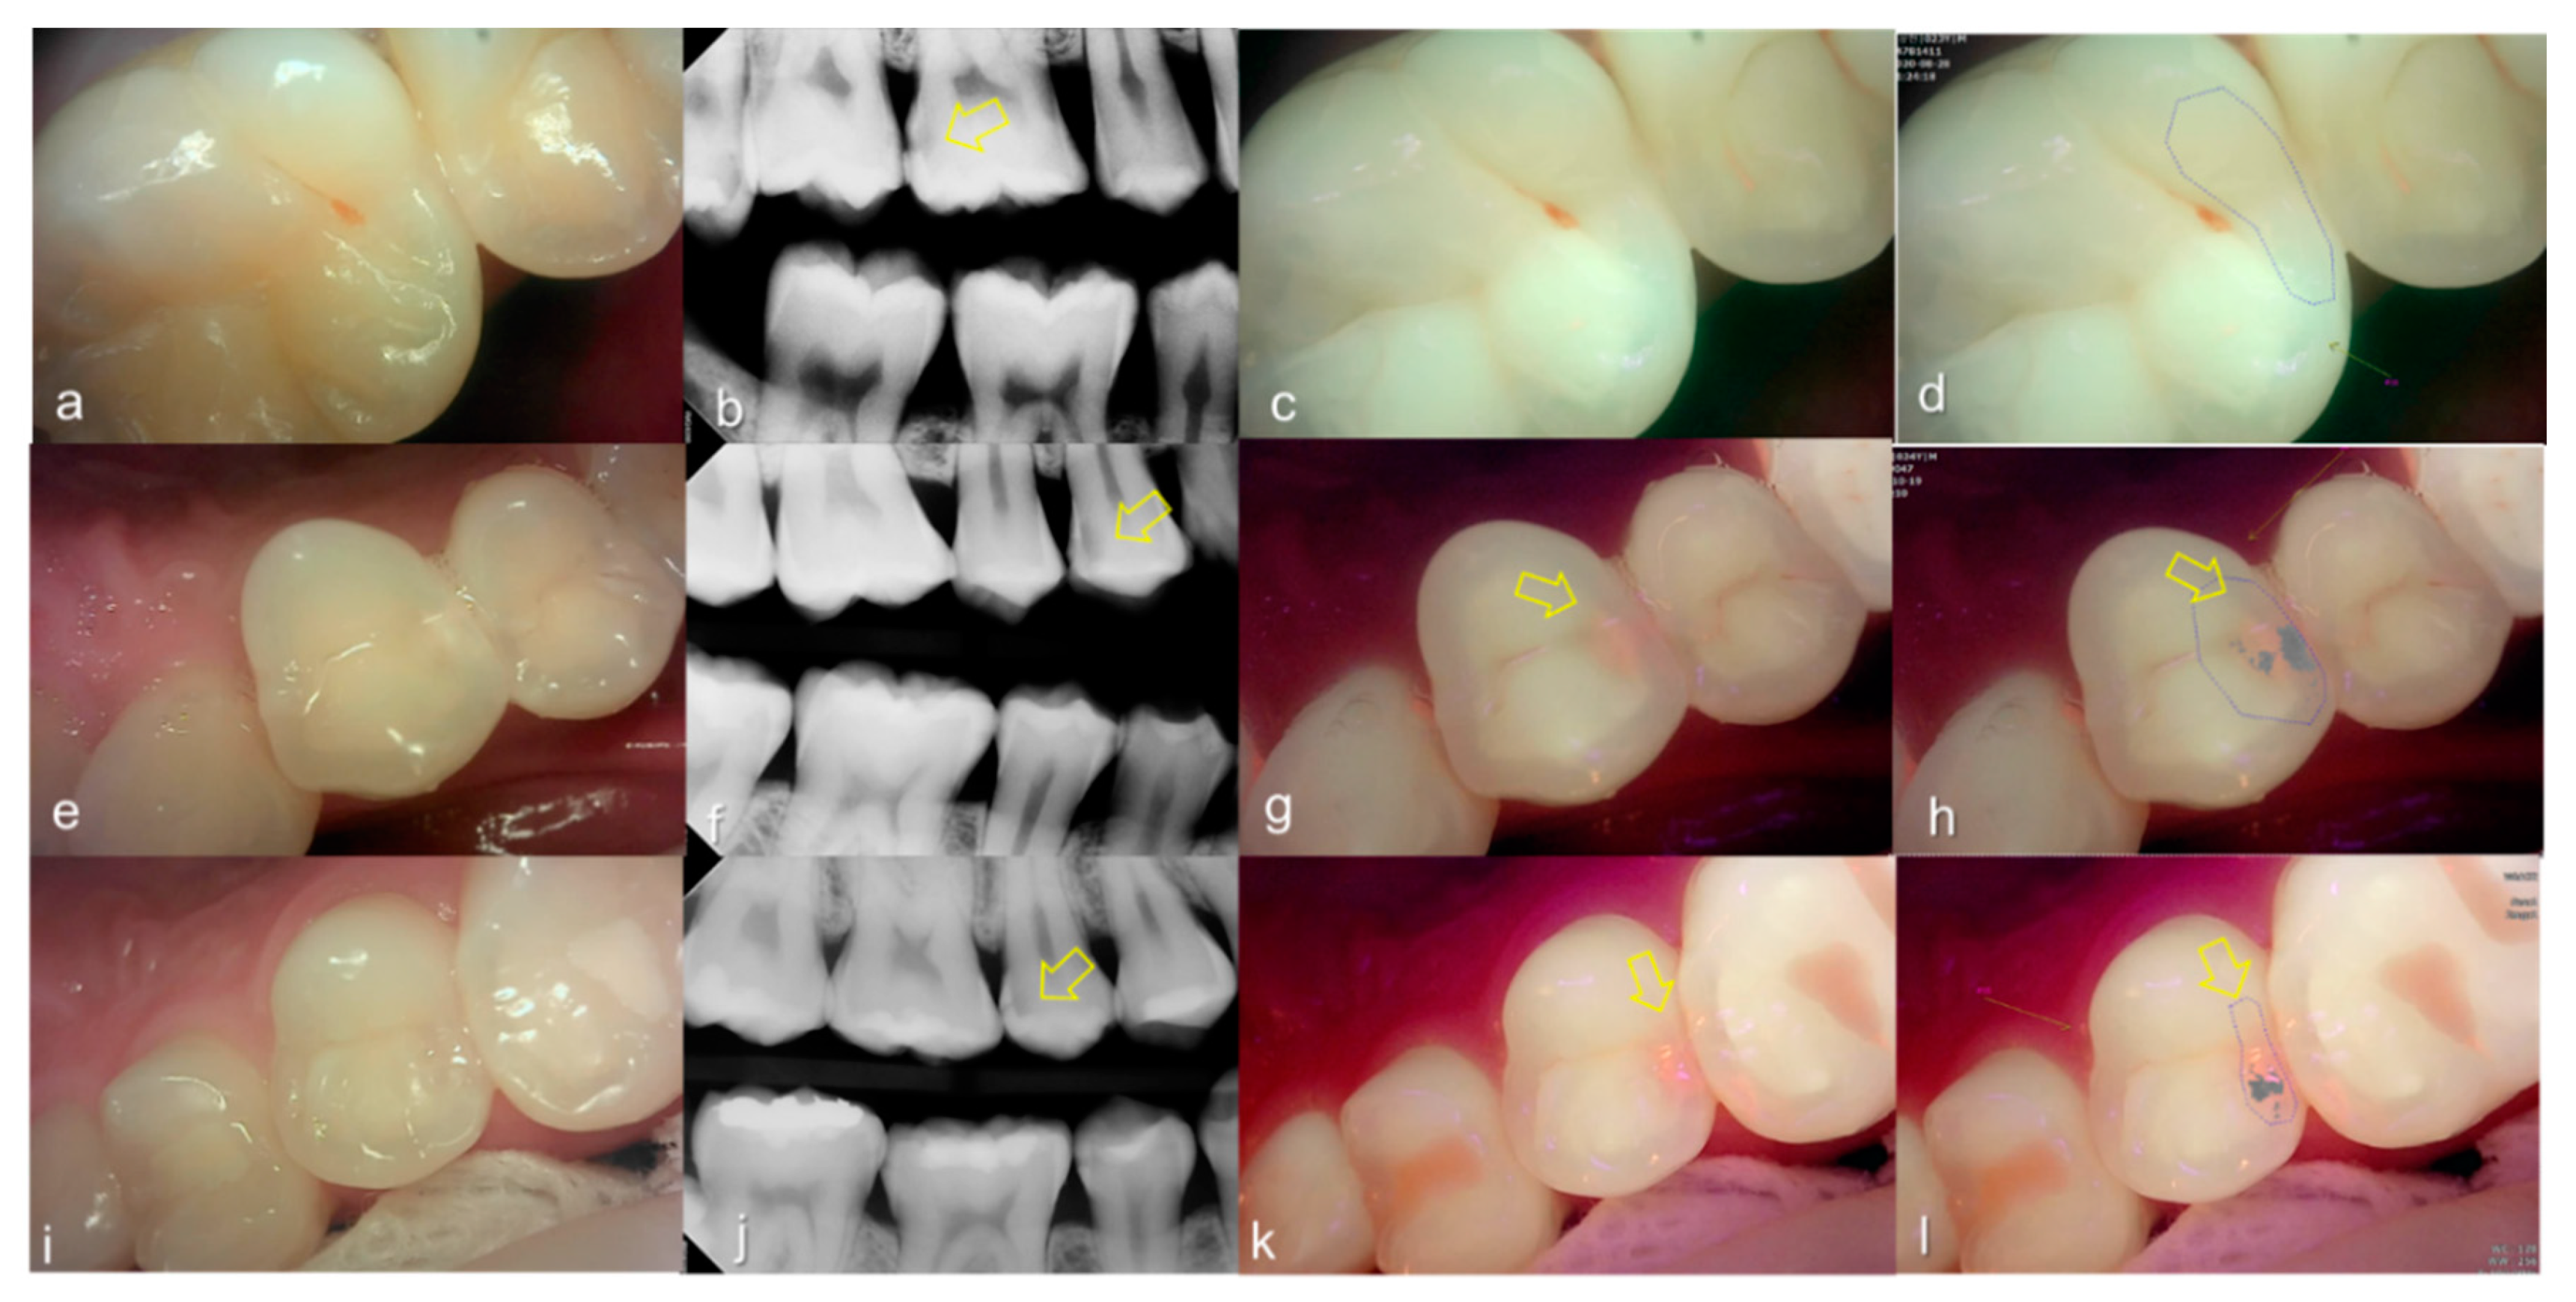

3.3. Crack

The values of the QLF parameter according to the value classified based on the QLF criteria were significantly different (Table 2). The cut-off value of |ΔFmax| and ΔRmax for determining a crack (QLF criteria scores 0 and 1 vs. 2) was 20.80 and 39.00, respectively. In addition, the AUROC of QLF parameters were similar (0.83, 0.82) (Table 3). Representative images of QLF and bitewing radiograph of dental cracks are shown in Figure 9 and Figure 10.

Figure 9.

Cracks: (a) white-light image of QLF, visual examination score 0 (No detectable crack line) on #15; (b) fluorescence image of QLF, QLF caries score 1 (fluorescence loss and red fluorescence present as a line in a crack site) on #15.

Figure 10.

Cracks: (a–d) QLF caries score 2 (fluorescence loss and red fluorescence glow extending around crack site) and visual examination score 0 (no detectable crack line) on #25; (e–h) QLF caries score 2 (fluorescence loss and red fluorescence glow extending around a crack site) and visual examination score 1 (ambiguous detectable crack line) on #17 (arrow 1), QLF caries score 1 (fluorescence loss and red fluorescence present as a line in the crack site) and visual examination score 0 (no detectable crack line) on #17 (arrow 2); (i–l) QLF caries score 2 (fluorescence loss and red fluorescence glow extending around a crack site) and visual examination score 2 (distinct detectable crack line) on #47; (a,e,i): white-light image of QLF; (b,f,j): fluorescence image of QLF; (c,g,k): bitewing radiograph; (d,h,l): analyzed QLF image using QA2 software.